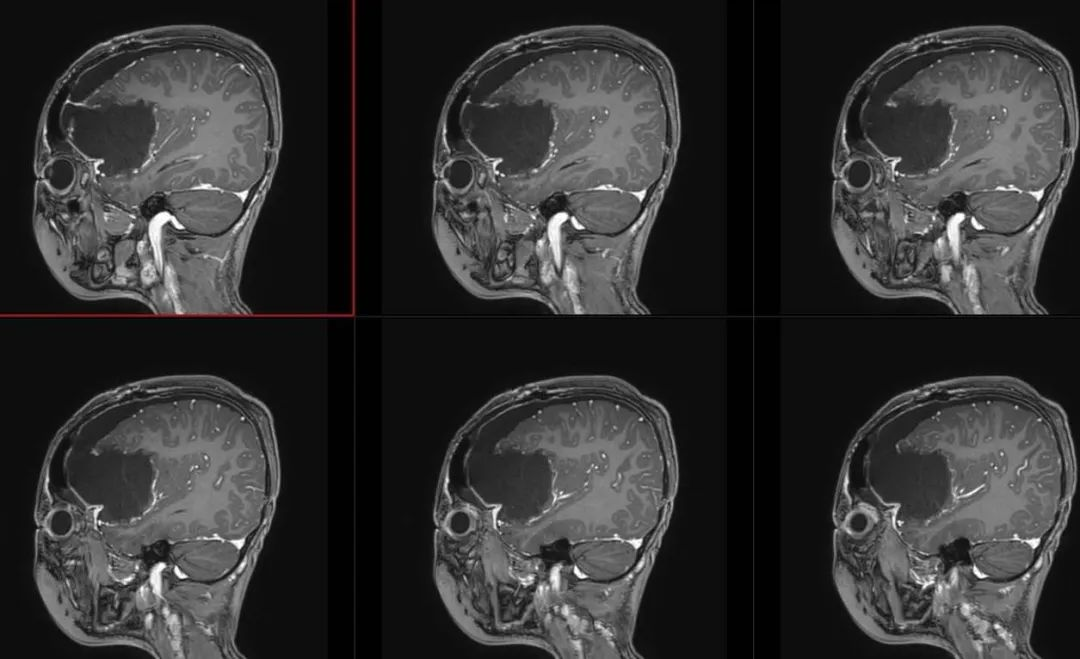

术前影像

术前颅脑CT囊实性占位

术前T1轴位

术前T1冠状位

术前FLAIR

术前T2轴位

术前T2矢状位

术前颅脑MRA、MRV

术前T1冠状位增强

术前T1轴位增强

术后第3天T2

术后FLAIR

术后T1冠状位增强

术后T1矢状位增强

术后T1轴位增强